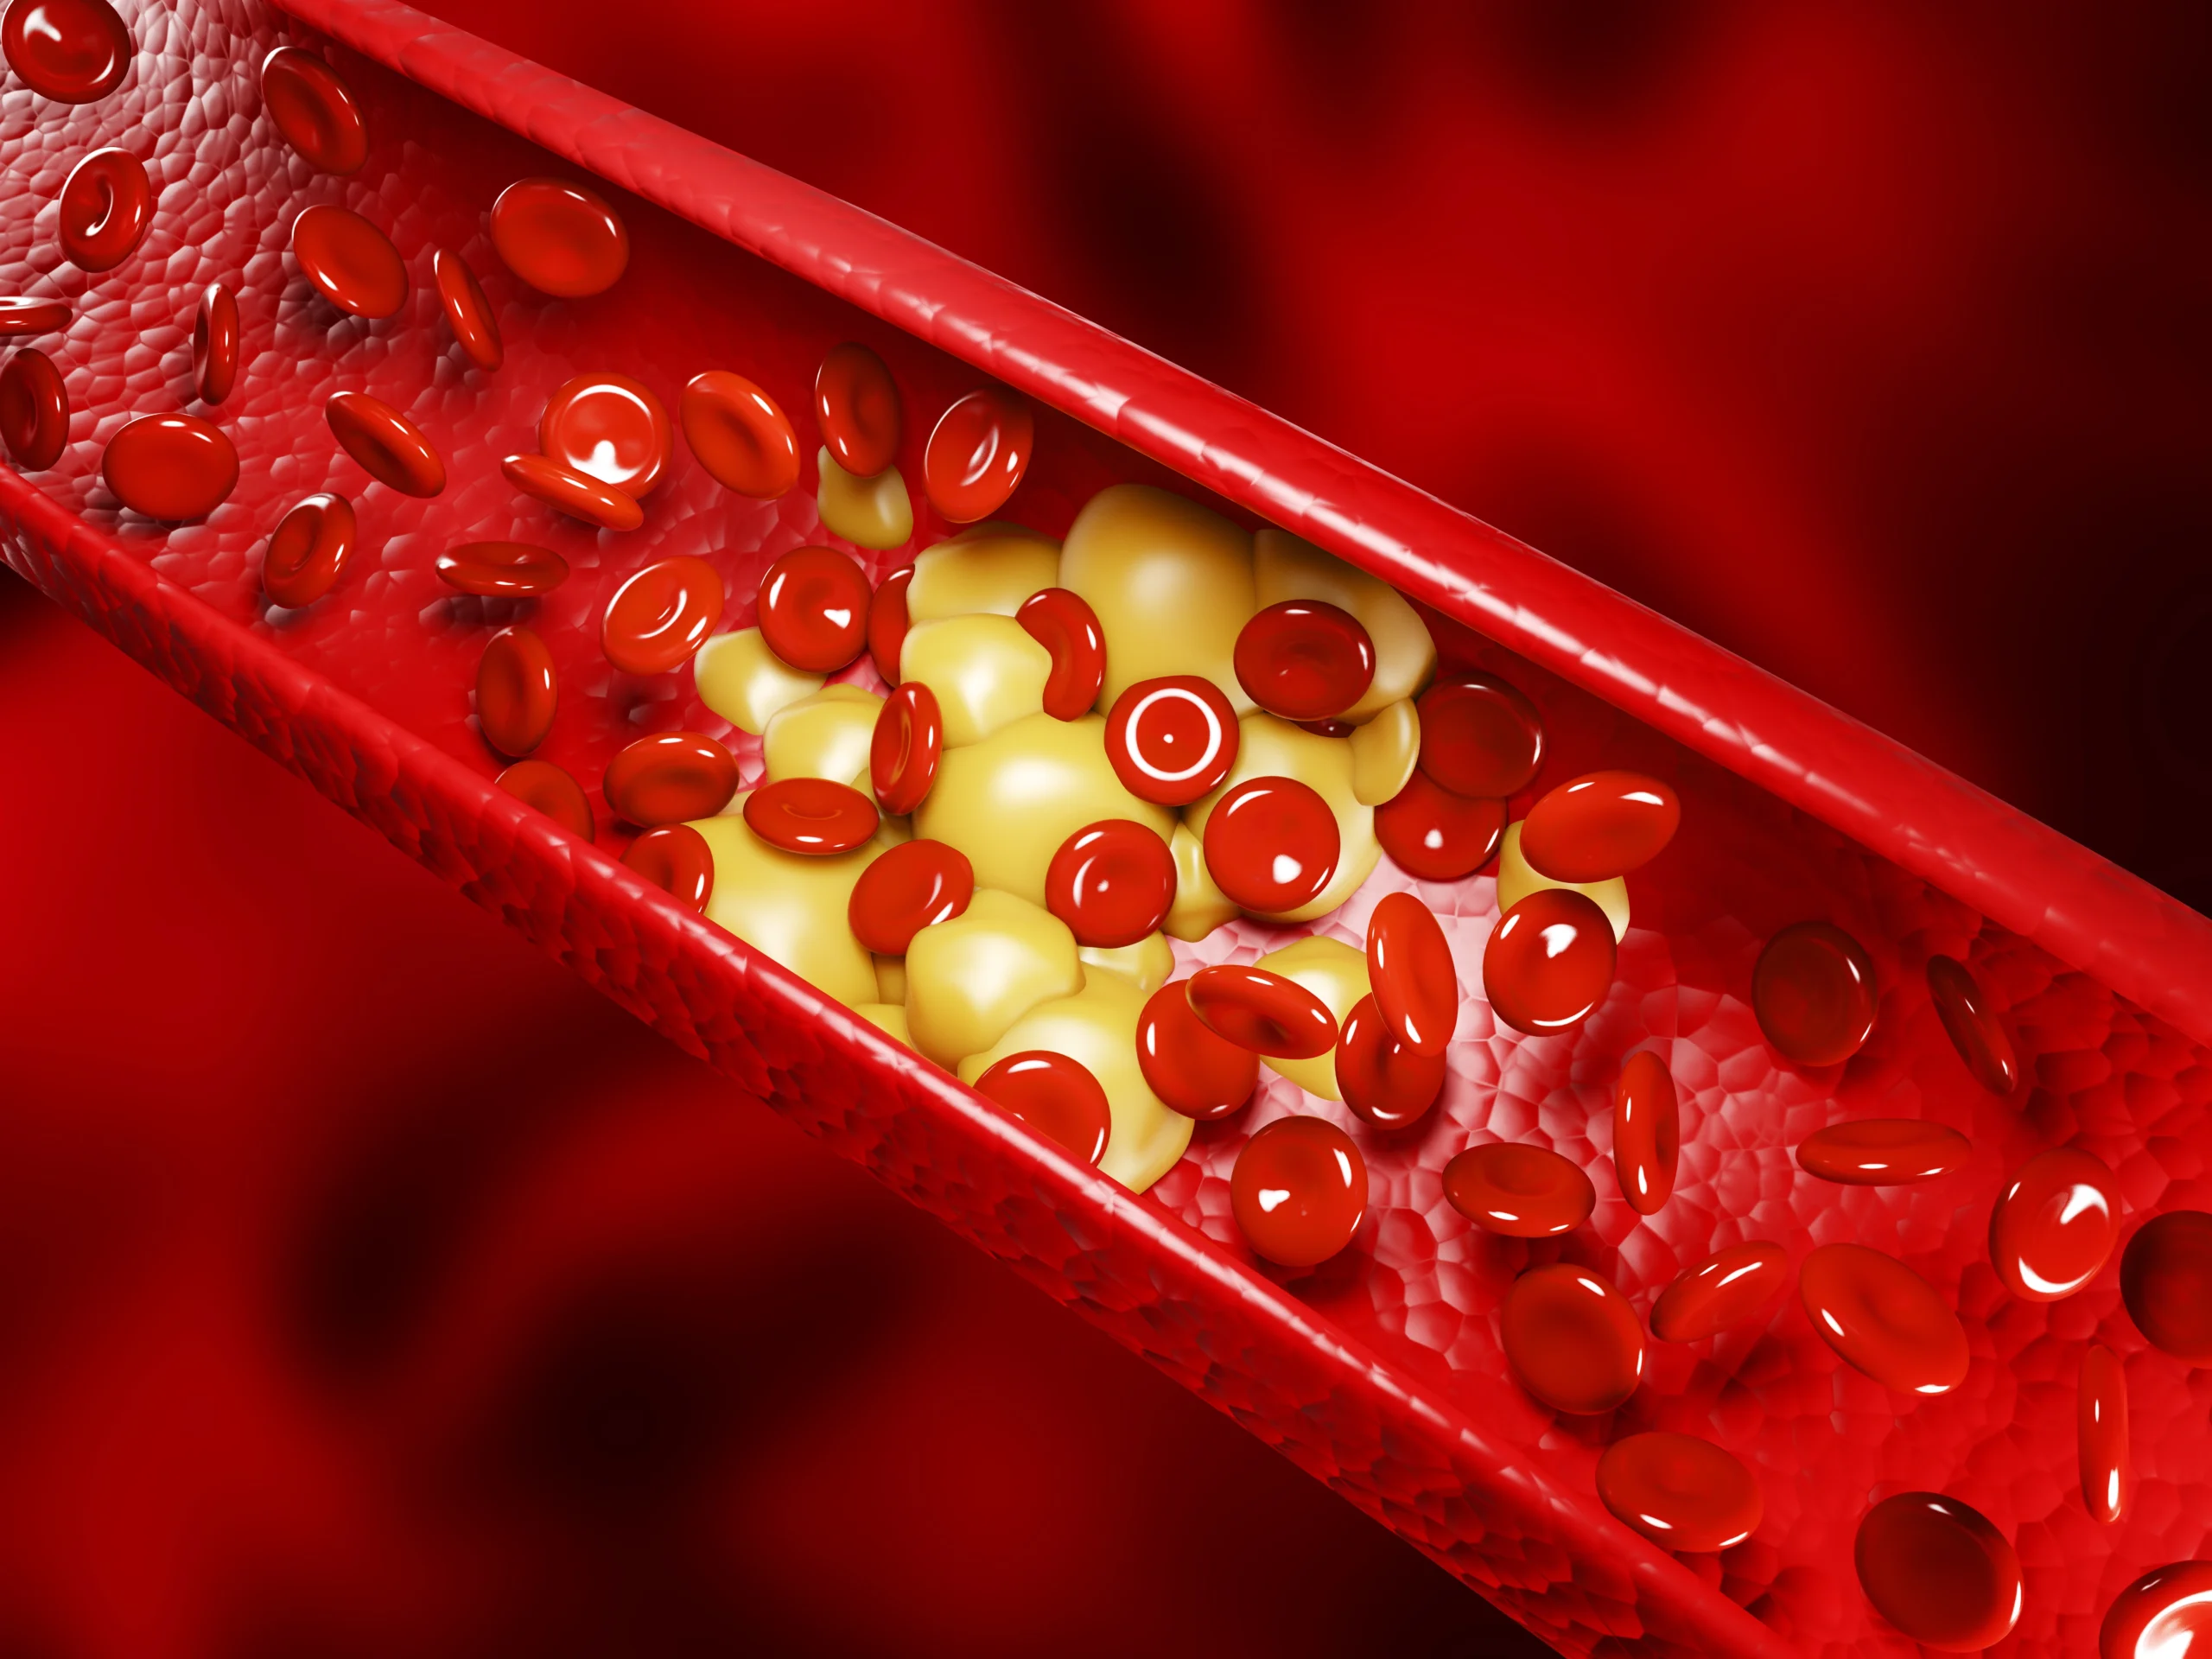

2. Hernia Nukleus Pulposus (HNP) / Saraf Terjepit

HNP terjadi ketika cakram intervertebralis (bantalan antar tulang belakang) mengalami kerusakan atau menonjol keluar, menekan saraf di sekitarnya.

Jika terjadi di tulang leher (servikal), maka menunduk bisa memperparah tekanan pada saraf yang sudah terjepit, menyebabkan nyeri yang menjalar ke bahu atau tangan.

Seiring bertambahnya usia, cakram tulang belakang mengalami degenerasi dan kehilangan elastisitasnya. Kondisi ini disebut cervical spondylosis, yang dapat menyebabkan pertumbuhan taji tulang (bone spur) dan mempersempit ruang bagi saraf (stenosis spinal).

Radikulopati terjadi ketika saraf yang keluar dari tulang belakang servikal terjepit atau mengalami iritasi akibat cakram yang menonjol, artritis, atau spondylosis.

8. Stenosis Spinal Servikal

Stenosis spinal terjadi ketika ruang di dalam kanal tulang belakang menyempit, menyebabkan tekanan pada sumsum tulang belakang dan saraf. Biasanya terjadi akibat penuaan atau cedera.

Salah satu penyebab nyeri leher yang lebih serius adalah cervical myelopathy, yaitu kondisi yang terjadi akibat penekanan pada sumsum tulang belakang di area leher.

Kondisi ini sering kali disebabkan oleh degenerasi tulang belakang yang berkaitan dengan usia, seperti herniasi diskus atau osteoarthritis.